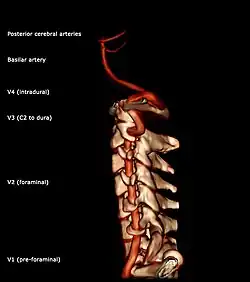

Segments of vertebral artery anterior projection

The vertebral artery may be divided into four parts:

• The first (preforaminal) part runs upward and backward between the anterior scalene and the longus colli muscles. In front of it are the internal jugular and vertebral veins, and is crossed by the inferior thyroid artery; the left vertebral is also crossed by the thoracic duct. Behind it are the transverse process of the seventh cervical vertebra, the sympathetic trunk and its inferior cervical ganglion

• The second (foraminal) part runs upward through the transverse foramina of the C6 to C2 vertebrae, and is surrounded by branches from the inferior cervical sympathetic ganglion and by a plexus of veins which unite to form the vertebral vein at the lower part of the neck. It is situated in front of the trunks of the cervical nerves, and pursues an almost vertical course as far as the transverse process of the axis.

• The third (extradural or atlantic) part issues from the C2 foramen transversarium on the medial side of the Rectus capitis lateralis. It is further subdivided into the vertical part V3v passing vertically upwards, crossing the C2 root and entering the foramen transversarium of C1, and the horizontal part V3h, curving medially and posteriorly behind the superior articular process of the atlas, the anterior ramus of the first cervical nerve being on its medial side; it then lies in the groove on the upper surface of the posterior arch of the atlas, and enters the vertebral canal by passing beneath the posterior atlantoöccipital membrane. This part of the artery is covered by the Semispinalis capitis and is contained in the suboccipital triangle—a triangular space bounded by the Rectus capitis posterior major, the Obliquus superior, and the Obliquus inferior. The first cervical or suboccipital nerve lies between the artery and the posterior arch of the atlas.

• Segments of vertebral artery lateral projection

The fourth (intradural or intracranial) part pierces the dura mater and inclines medially to the front of the medulla oblongata; it is placed between the hypoglossal nerve and the anterior root of the first cervical nerve and beneath the first digitation of the ligamentum denticulatum. At the lower border of the pons, it unites with the vessel of the opposite side to form the basilar artery.